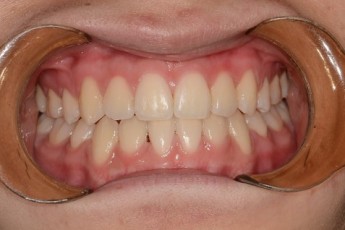

BEFORE & AFTER